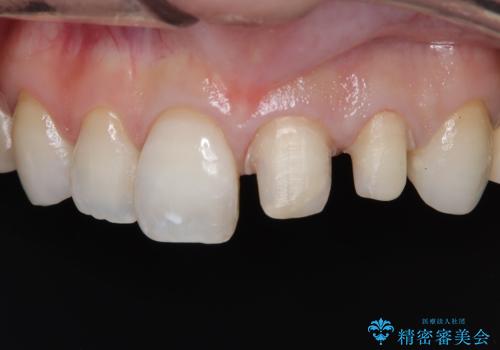

- 「前歯の色が気になる」を主訴に来院された患者さんです。以前他院にて、前歯2本をCR(プラスチック)で治療されていたところが劣化し変色していました。歯の長さも左右で異なっている状態でした。大部分がCR(プラスチック)修復されていたので、オールセラミッククラウンで治療を行いました。

古いCR(プラスチック)とその下の虫歯を除去した後に新しい土台を立てています。適合が良い被せ物を作るために拡大鏡を使用しながら歯を削り、変形のほとんどないシリコンという材料で型取りを行っています。